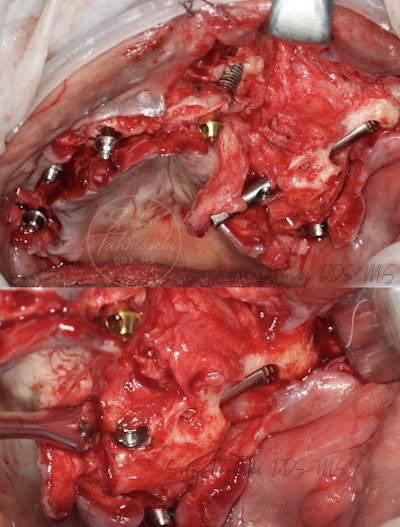

Figure 4: John Doe's existing teeth were extracted and replaced with a maxillary full-arch implant.

Figure 6. The maxillary full-arch dental implant.